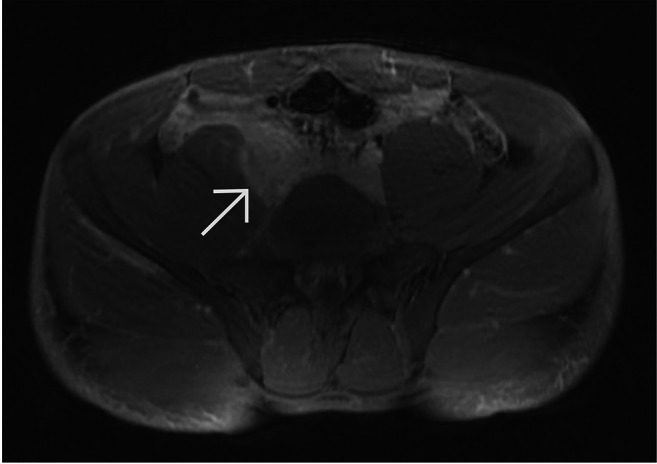

Background/aim: Immunoglobulin G4-related disease (IgG4-RD) is a systemic, immune-mediated condition characterized by fibroinflammatory lesions affecting multiple organs. When localized in the retroperitoneum, it may mimic malignancy and often leads to surgical intervention. We report the case of a 21-year-old male with retroperitoneal IgG4-RD and review the relevant literature, emphasizing the diagnostic challenges and importance of differential diagnosis.

Results: Of 74 articles retrieved, 22 met the inclusion criteria, totaling 23 patients including our case. The mean age was 62 years, with a male predominance (65%). The left ureter was most commonly involved (52%). Frequent symptoms included localized abdominal pain (61%) and hydronephrosis (96%). Imaging often suggested malignancy, leading 74% of patients to undergo surgery. Histopathology confirmed IgG4-RD in all cases, though only 30% showed IgG4 immunohistochemical positivity.

Conclusion: Retroperitoneal IgG4-RD closely mimics malignancy, posing significant diagnostic challenges. Elevated serum IgG4 levels and tissue biopsy are critical for accurate diagnosis. IgG4-RD should be considered in patients with unexplained retroperitoneal masses to avoid unnecessary surgery and ensure appropriate treatment.